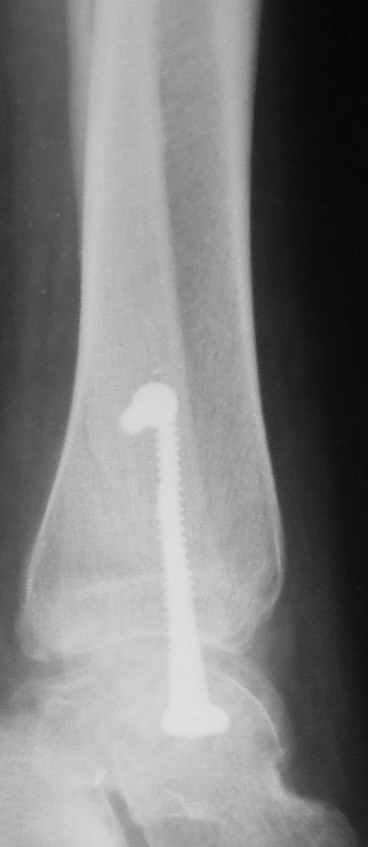

15 ноября прямой

15 ноября боковой

15 ноября трехчетвертной